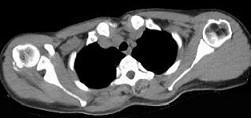

女,47岁,右肩部疼痛并肩关节活动受限数月,请结合所提供的图像,选择最佳选项 ( )A、未见明显异常B、肩周炎C、颈部肿瘤D、...

问题 女,47岁,右肩部疼痛并肩关节活动受限数月,请结合所提供的图像,选择最佳选项 ( )

选项 A、未见明显异常 B、肩周炎 C、颈部肿瘤 D、化脓性肩关节炎 E、颈椎病

答案 B